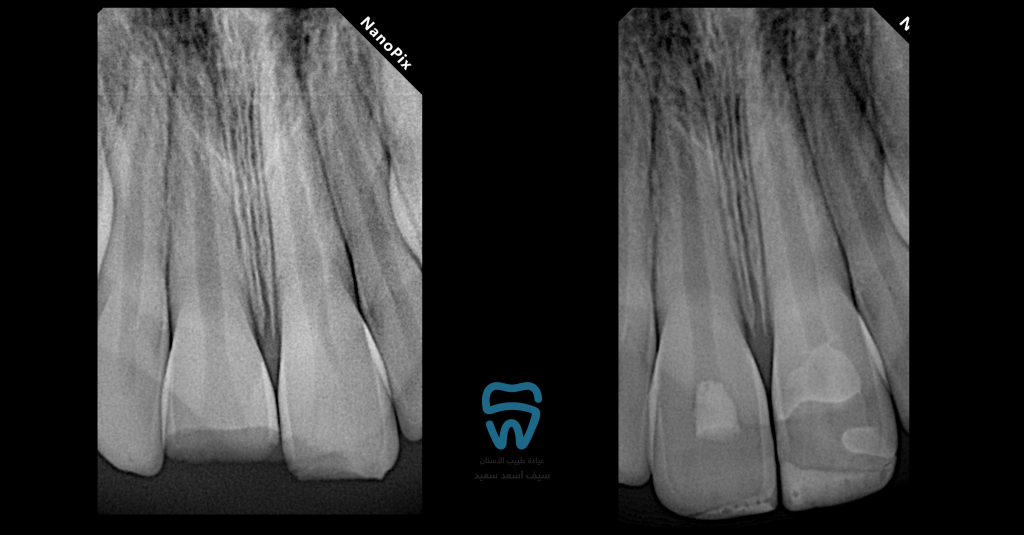

Pre and post operative radiographs